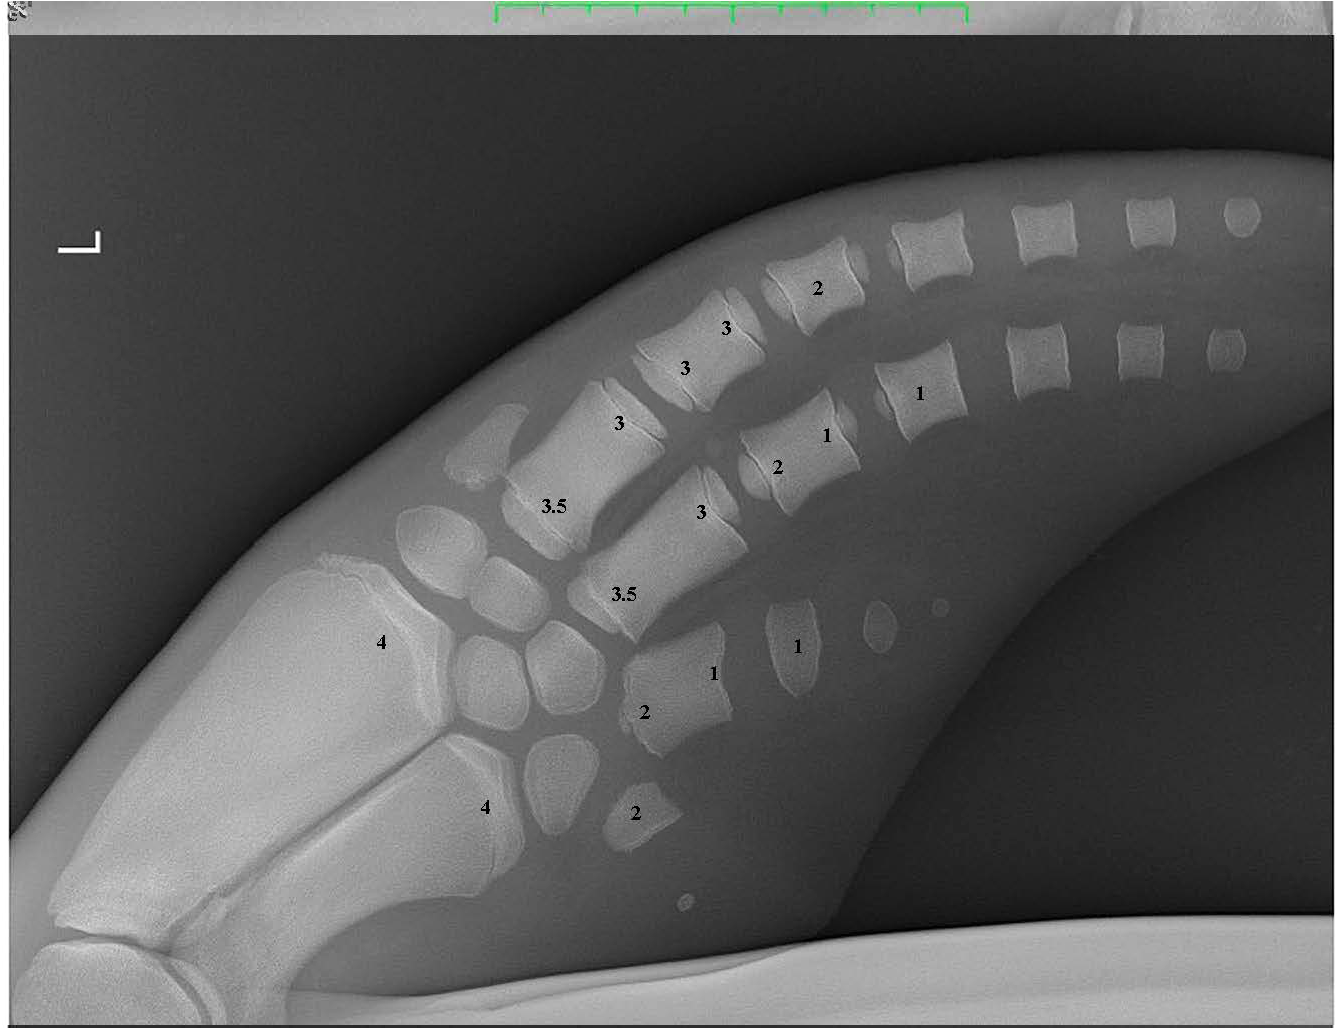

Validation of the GLG technique has not previously been possible in dolphins over 16 years of age due to a lack of samples available from known aged dolphins (Hohn et al., 1989). Despite the well-documented limitations of tooth aging, GLG tooth aging remains the primary method to estimate the age of wild bottlenose dolphins due to the insufficiency of alternative aging techniques. Alternative methods to estimate age have included morphometrics such as total straight length, however the asymptotic nature of dolphin growth curves results in length being an inaccurate assessment of age in older animals (Mcfee et al., 2012). More recently, dental radiography was demonstrated as a viable alternative to tooth extraction, however accuracy in age estimation decreased significantly in dolphins > 11 years of age, therefore this technique could not be used across the dolphin’s full lifespan (Herrman et al., 2020). Bone density was extensively researched but unfortunately did not provide an accurate correlation with age (Powell et al., 2019). Pectoral flipper radiography is highly accurate in young animals up to adulthood, but relies upon degenerative osteoarthritic changes to accurately estimate age in older individuals when all bone growth plates are fully consolidated. Therefore flipper radiography becomes more subjective in dolphins >25 years of age (Barratclough et al., 2019a) (Figure 3). Epigenetics via DNA methylation is a promising new technology to accurately estimate age, and may be applicable across the dolphin’s lifespan (Barratclough et al., 2021; Peters et al., 2022).

Figure 3 A pectoral flipper radiograph demonstrating the open physeal plates present in a young sexually immature dolphin. The scores for each of the 16 locations are provided on the radiograph. L, Left pectoral flipper.

A total of 37 pectoral flipper radiographs (PFR) were obtained from 36 dolphins; 12 from MMP dolphins, 10 from Sarasota health assessments and 15 from stranded dolphins in Sarasota Bay, following previously published techniques (Barratclough et al., 2019a). Radiographs can be taken of either flipper and a dorsal ventral view of the flipper including the distal radius to the distal phalanges (Figure 2). Of the 37 radiographs 13 were from females and 24 were from males. Of the 12 MMP dolphins, nine were known age from observed birth. Two had age estimated between 2-4 years of age based on morphometrics at the time of acquisition and one animal was estimated as 3yrs by GLG. Of the 25 Sarasota cases, 20 were known age from observed birth and five were known minimum age. In addition, 10 pectoral flipper radiographs were taken during 2019 and 2022 Sarasota Bay live dolphin health assessments, with one individual radiographed in both 2019 and 2022. Nine of these cases had known age and one individual was known minimum age. Of the 15 stranded cases, six were of known age and four had previous sighting data providing a minimum age estimate. Figure 4 depicts four radiographs with suggested scores for the growth plates and the given ages of the different stages allowing depiction of the predicted sequential changes in growth plate closure over time.

Radiographs were obtained as part of routine animal care under the authorization of U.S. Code, Title 10, USC 7524. Secretary of Navy Instruction 3900.41H directs that Navy marine mammals be provided the highest quality of care. The U.S. Navy Marine Mammal Program (MMP), Naval Information Warfare Center (NIWC) Pacific, houses and cares for a population of bottlenose dolphins and California sea lions in San Diego Bay (CA, USA). The MMP is accredited by AAALAC International and adheres to the national standards of the U.S. Public Health Service Policy on the Humane Care and Use of Laboratory Animals and the Animal Welfare Act. Pectoral flipper bone maturation scores were assigned independently by two blind reviewers, both marine mammal veterinarians with experience of the previously published technique (A.Barratclough and D. Garcia-Parraga). The established methodology requires a score of -1 to 8 to be applied to 16 different anatomic locations within the pectoral flipper with each score denoting the degree of development of the growth plate (Barratclough et al., 2019a). The metaphyseal region of the radius and ulna are the most informative along with the proximal and distal epiphysis of metacarpals II and III. The sex-specific equations reported by Barratclough et al. (2019a) were applied to predict the chronological age:

Sex-specific equations are required due to the different growth rates between male and female bottlenose dolphins and the different ages at which sexual and skeletal maturity occur. For example closure of the female radius growth plate is expected at 6-8 years whereas in males this does not occur until 10-12 years. By including 16 different scoring locations, the accuracy of age prediction is improved. Scores from the two reviewers were combined to provide an average age estimation for each individual. The known ages of the animals included for pectoral radiographs ranged from 0 – 58 years of age.